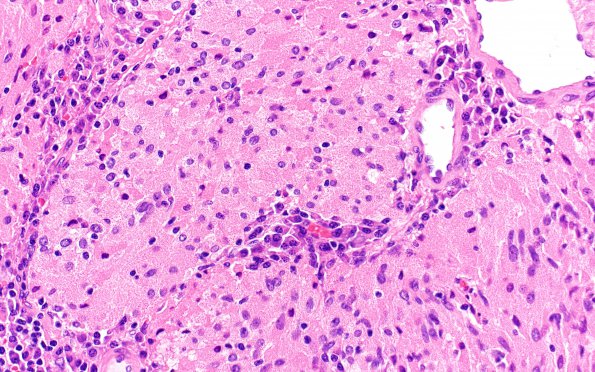

3B4 TTF1 Pituicytoma (Case 3) H&E 40X 3

Higher magnification tumor image (H&E)